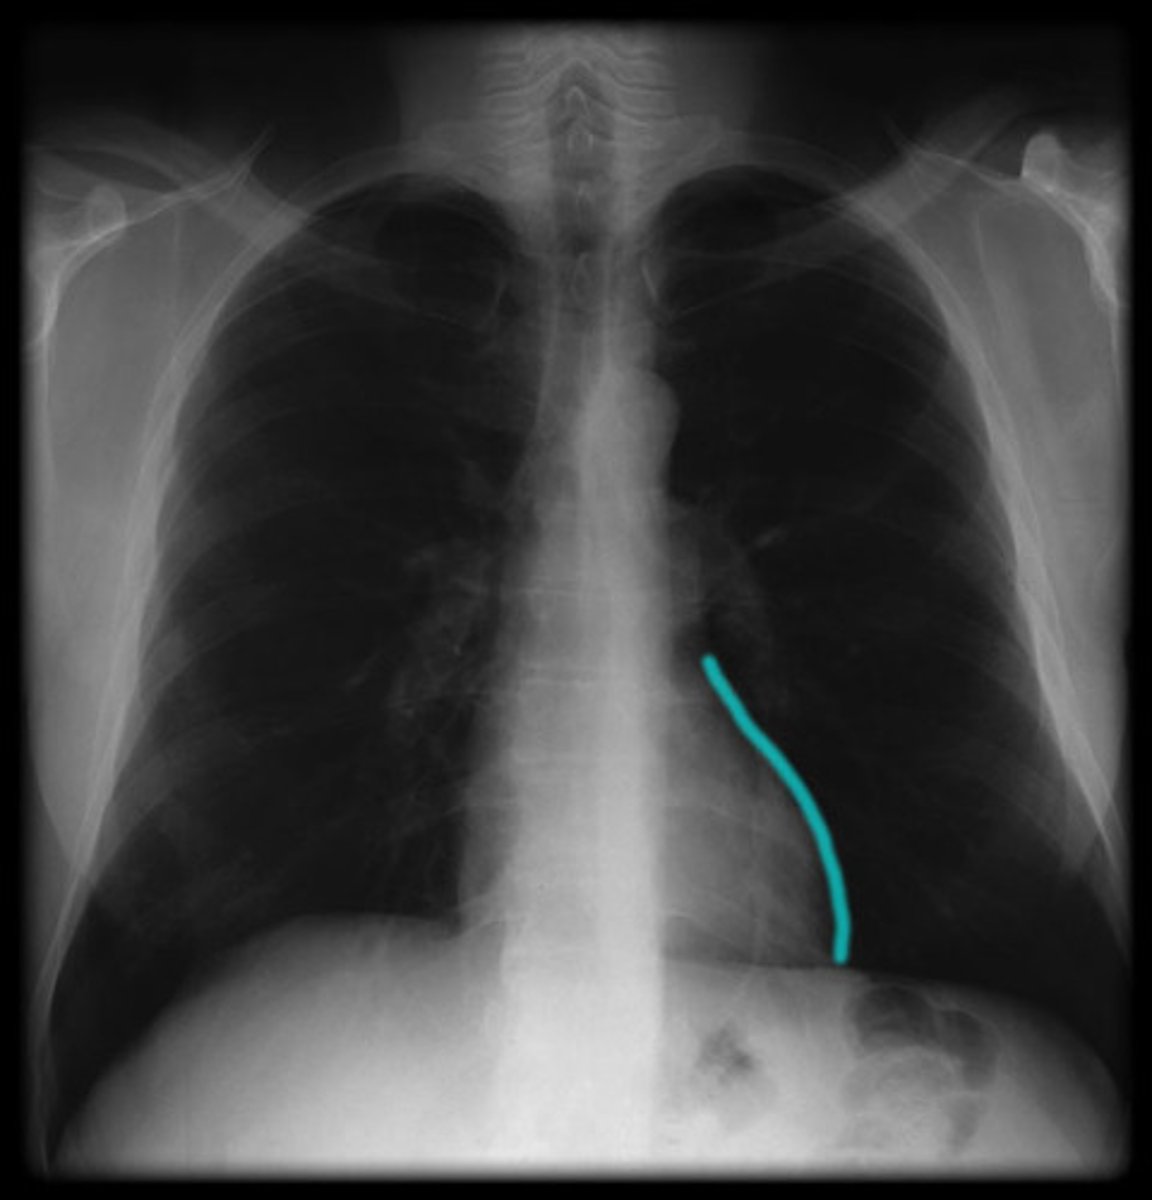

posterior interventricular sulcus

depression. posterior of the heart